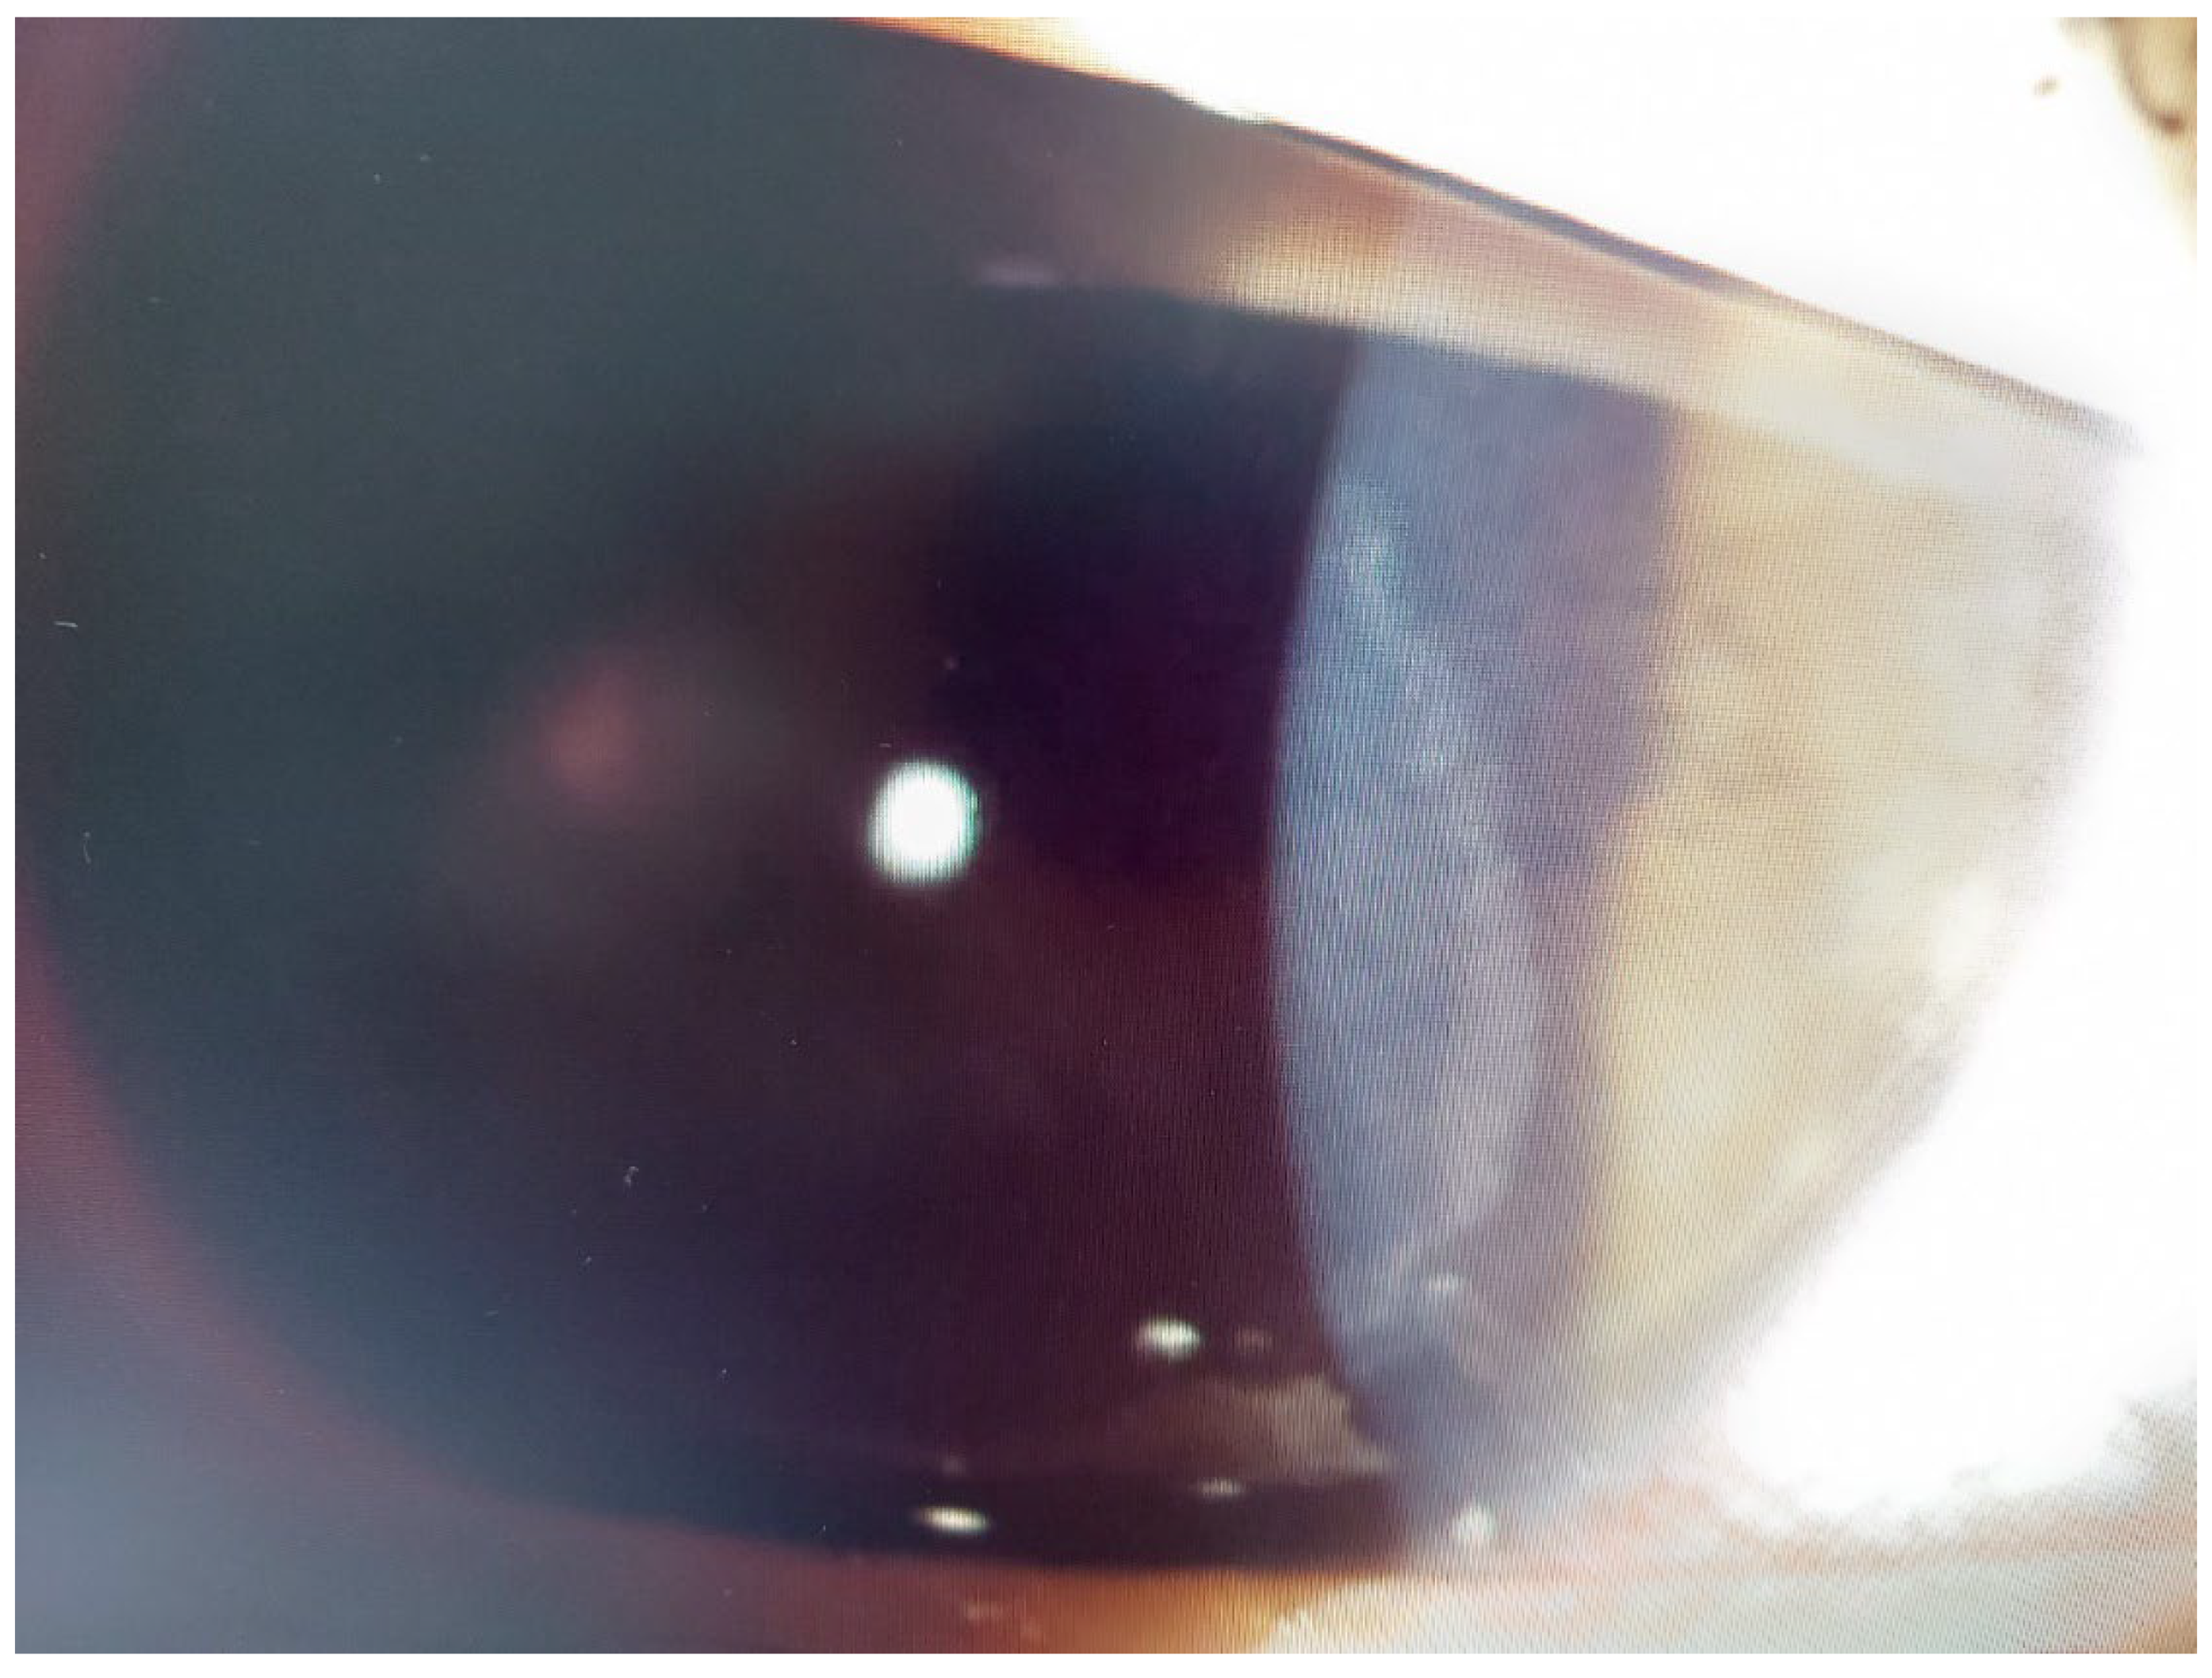

Infectious Keratitis Post-Femtosecond LASIK

Patient #1